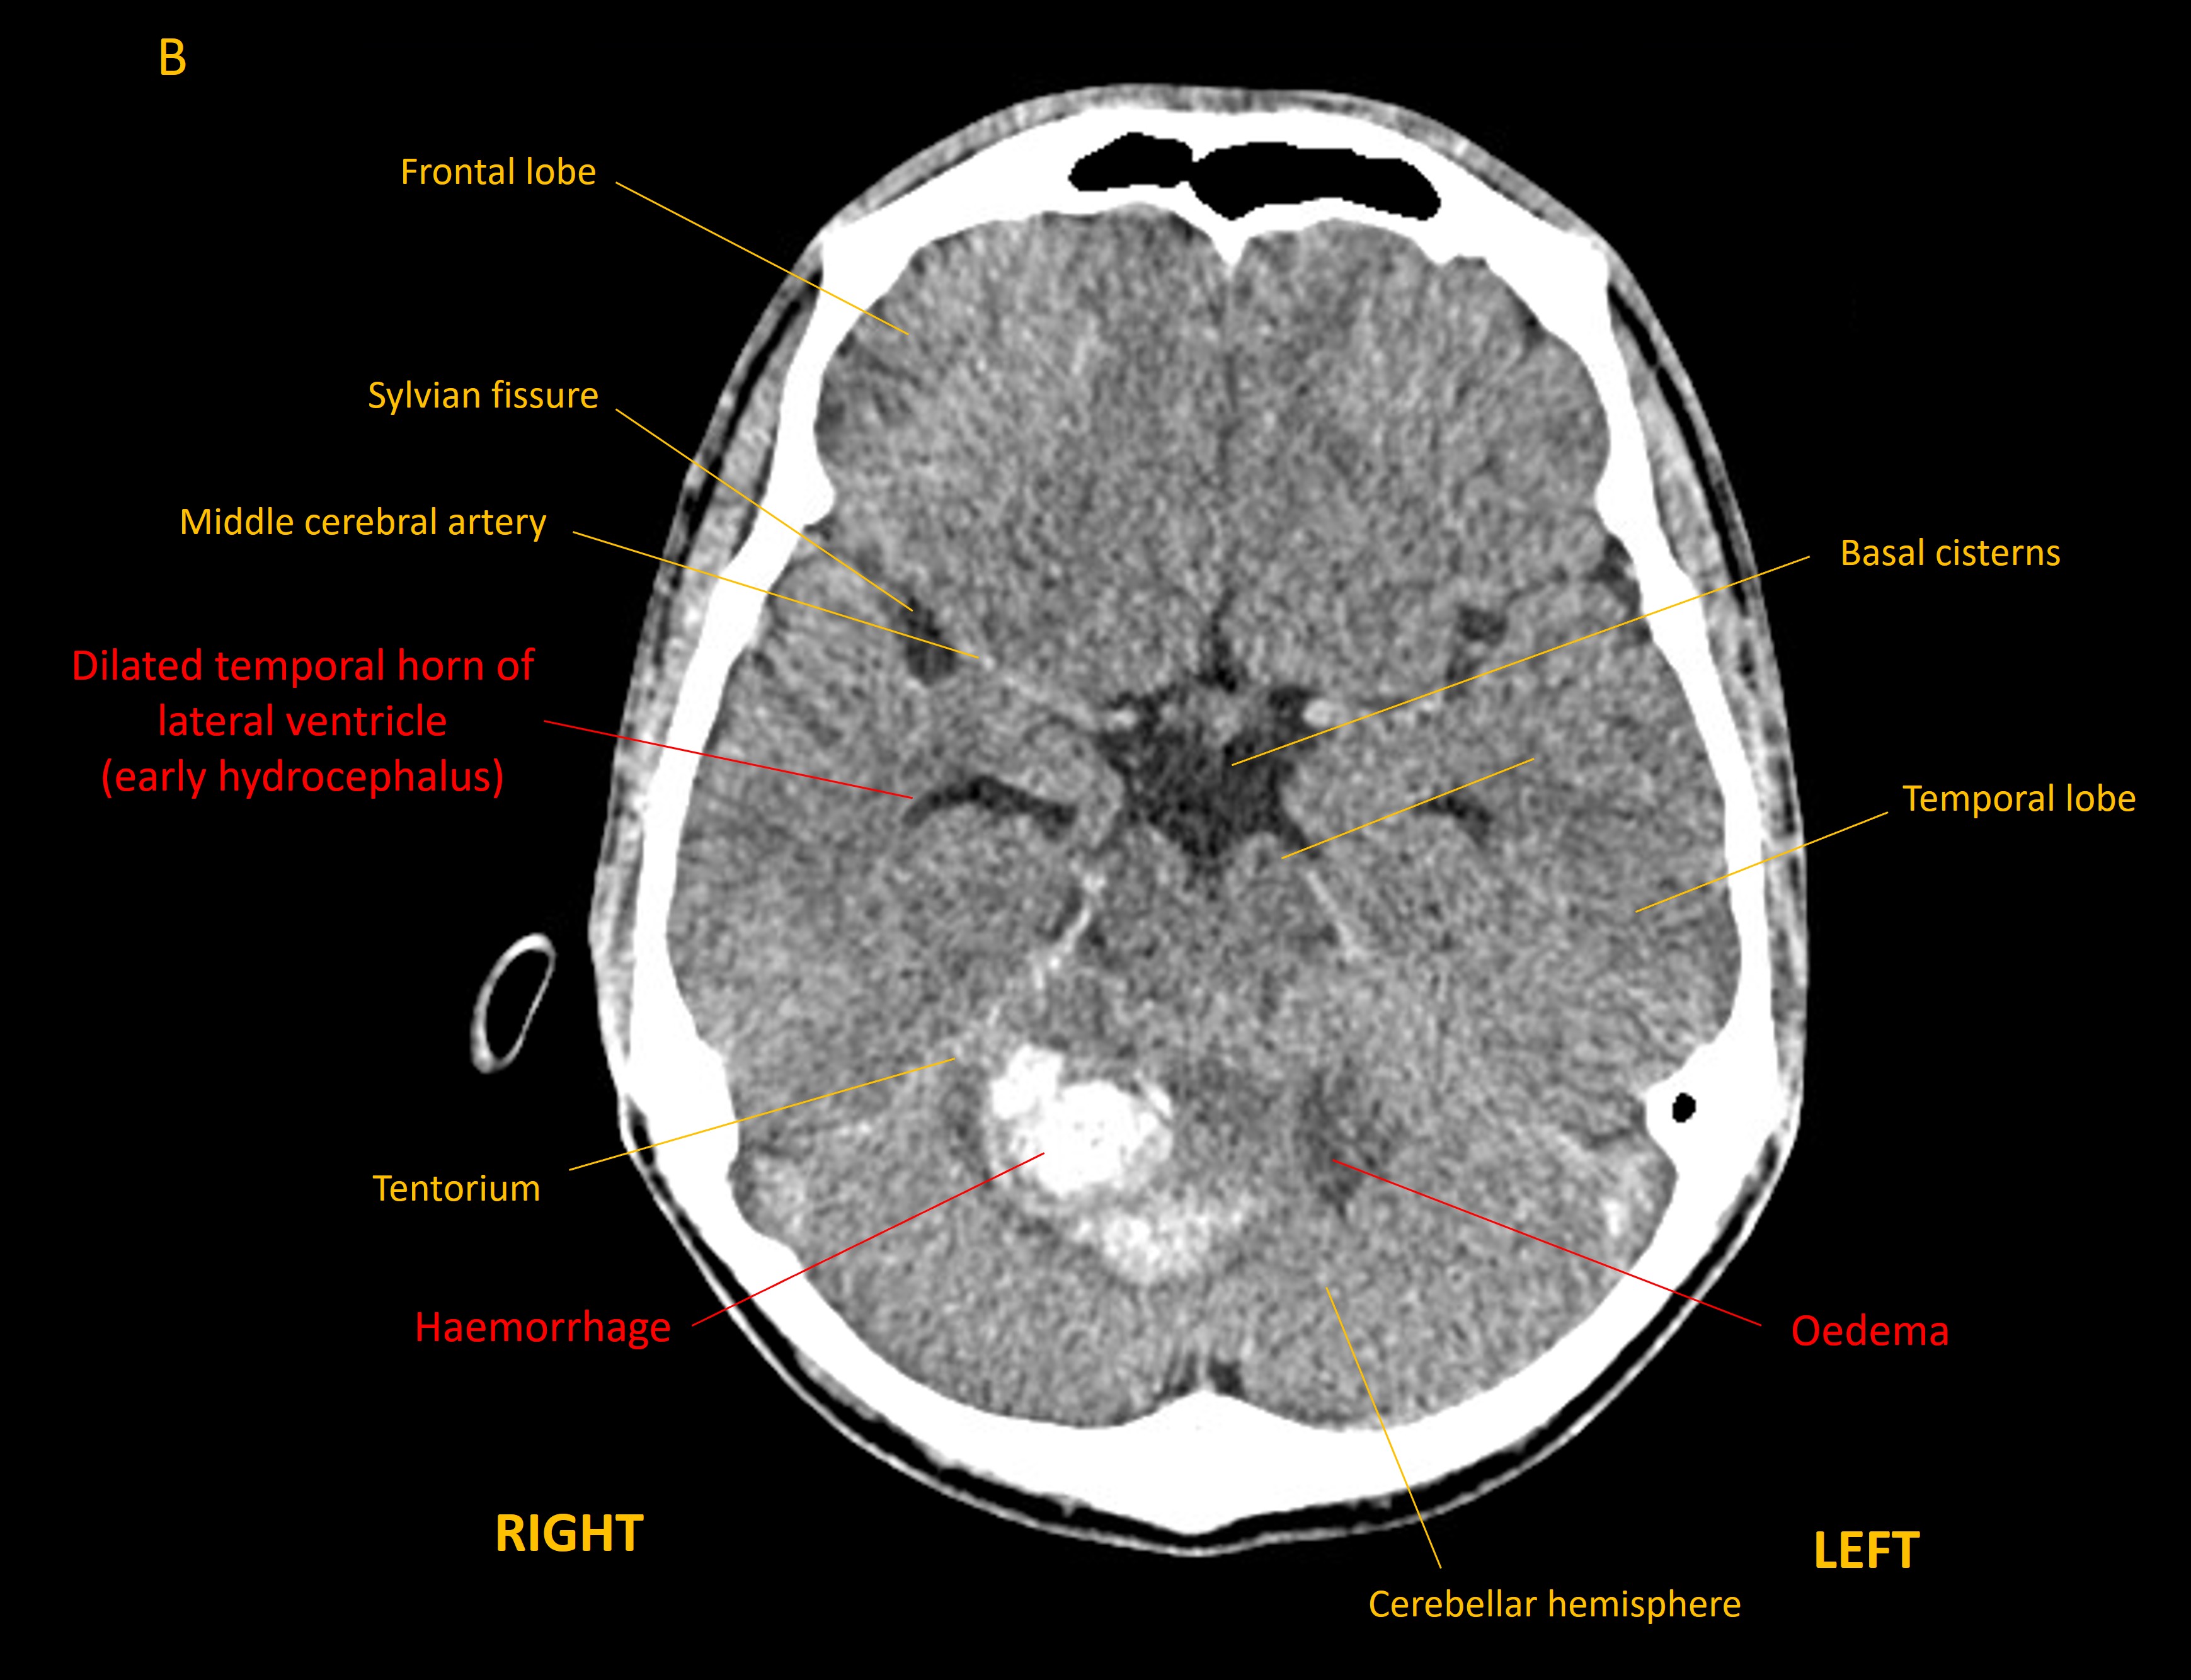

However, he deteriorated 5 weeks later, with headache, vomiting, vertigo, worsening ataxia (walking as if drunk), and dysarthric speech. CT imaging showed hydrocephalus developing - with dilatation of the temporal horns of the lateral ventricles - as well as effacement of the fourth ventricle lower down.

Axial CT brain